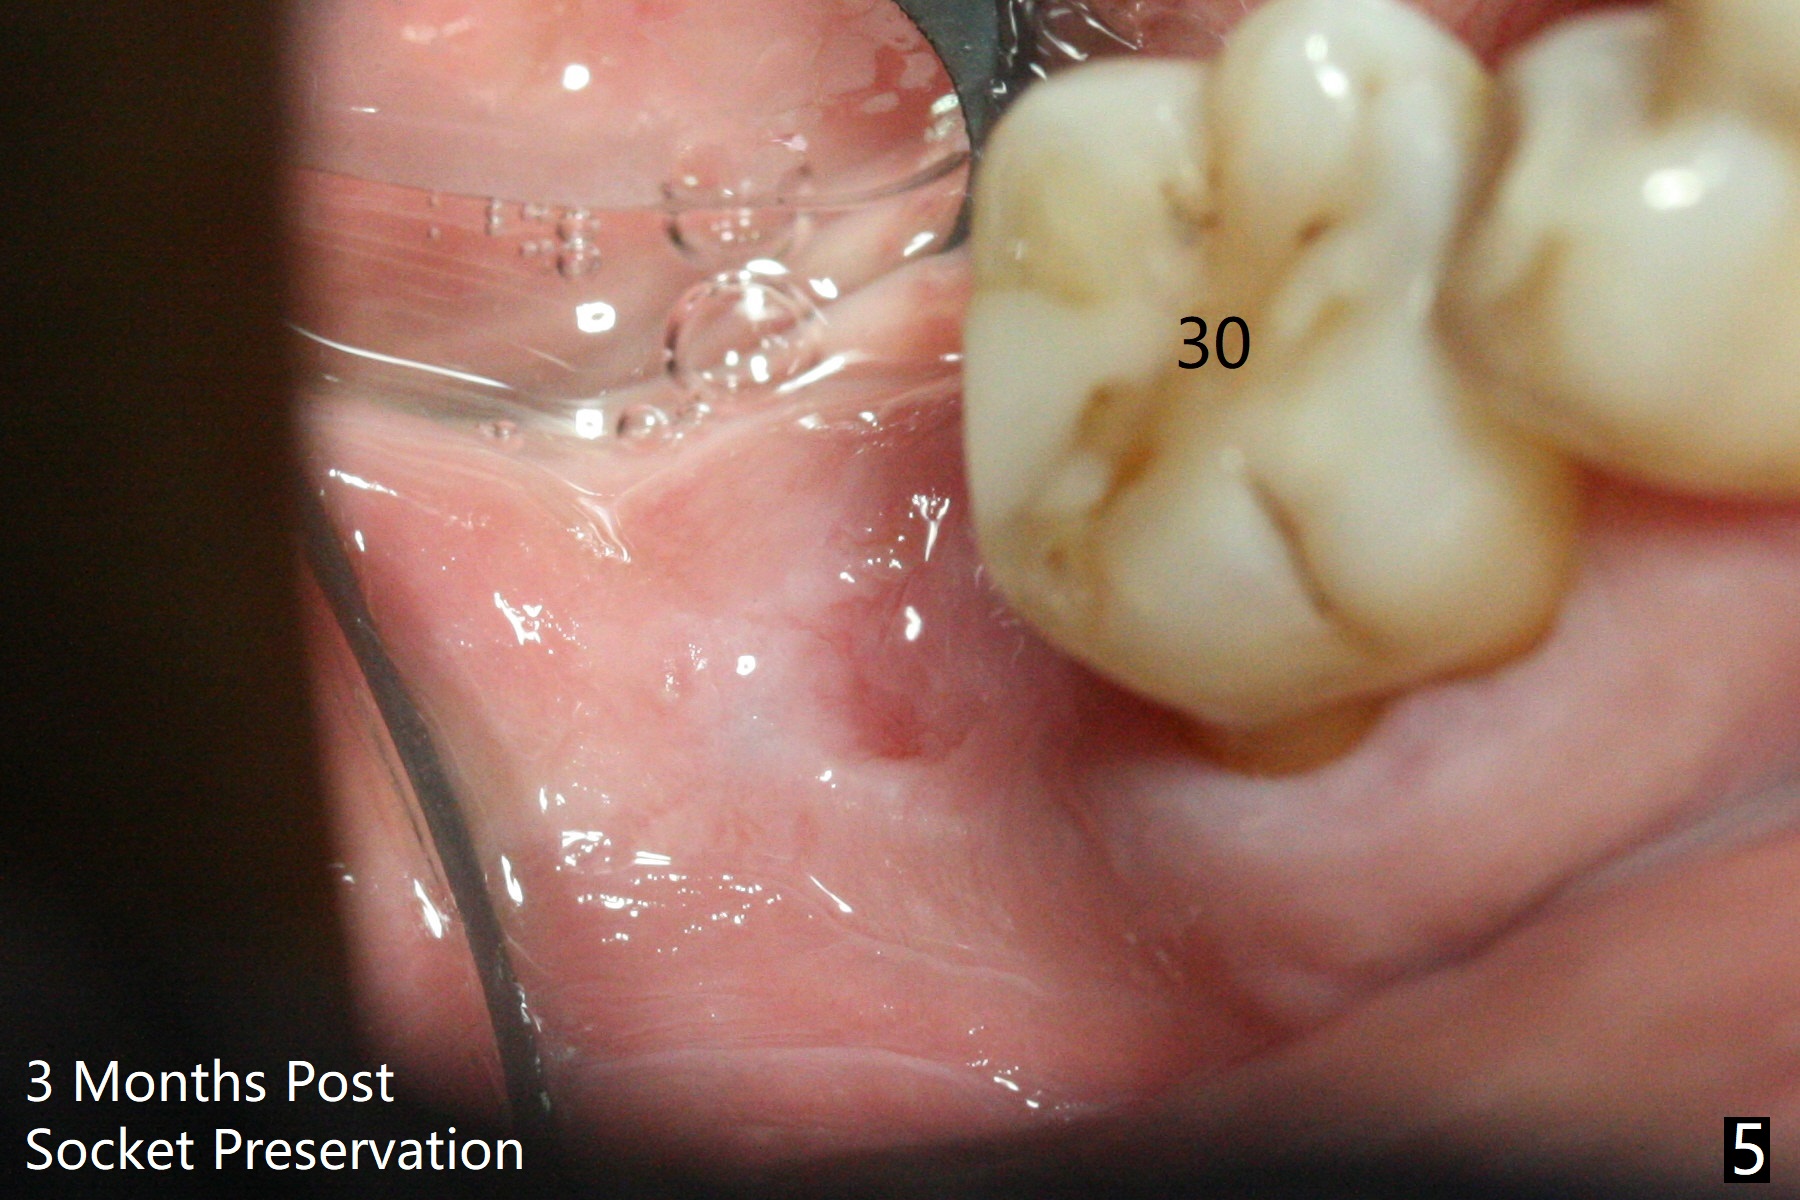

The socket shrinks with buccal plate reduction 3 months post socket preservation (Fig.5), as compared to 10 days postop (Fig.4). To restore the socket as much as possible, Magic Split is used (flapless), followed by Magic Expanders 3-3.8 mm for 11 mm (gingival level) and a 4x11mm dummy implant (Fig.6). The osteotomy is moved distal by using Lindamann bur; following 3.8 mm Magic Drill, a 4.5x11 mm dummy implant (Fig.7). Finally a definitive 5.5x9 mm implant is placed with <45 Ncm; a 6x2 mm healing abutment is placed to close the access (Fig.8). Autogenous bone harvested from the Magic Drill returns to the osteotomy mainly buccal prior to implant placement (Fig.8 *). The patient reports no discomfort immediately postop, thanks to the flapless technique. The patient has had postop pain; 11 days postop, the abutment and implant are found to be loose. After re-tightening by hand, the complex is seated deeper and more stable (Fig.9 arrow).